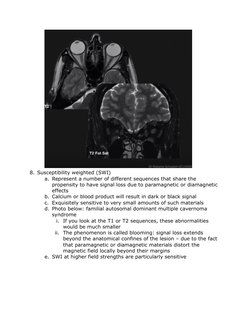

8. Susceptibility weighted (SWI)

a. Represent a number of different sequences that share the

propensity to have signal loss due to paramagnetic or diamagnetic

effects

b. Calcium or blood product will result in dark or black signal

c. Exquisitely sensitive to very small amounts of such materials

d. Photo below: familial autosomal dominant multiple cavernoma

syndrome

i. If you look at the T1 or T2 sequences, these abnormalities

would be much smaller

ii. The phenomenon is called blooming: signal loss extends

beyond the anatomical confines of the lesion due to the fact

that paramagnetic or diamagnetic materials distort the

magnetic field locally beyond their margins

e. SWI at higher field strengths are particularly sensitive

f. Susceptibility sensitive sequences gradient echo imaging

g. May deserve their own column but placed under T2-weighted

because many of these are T2* weighted